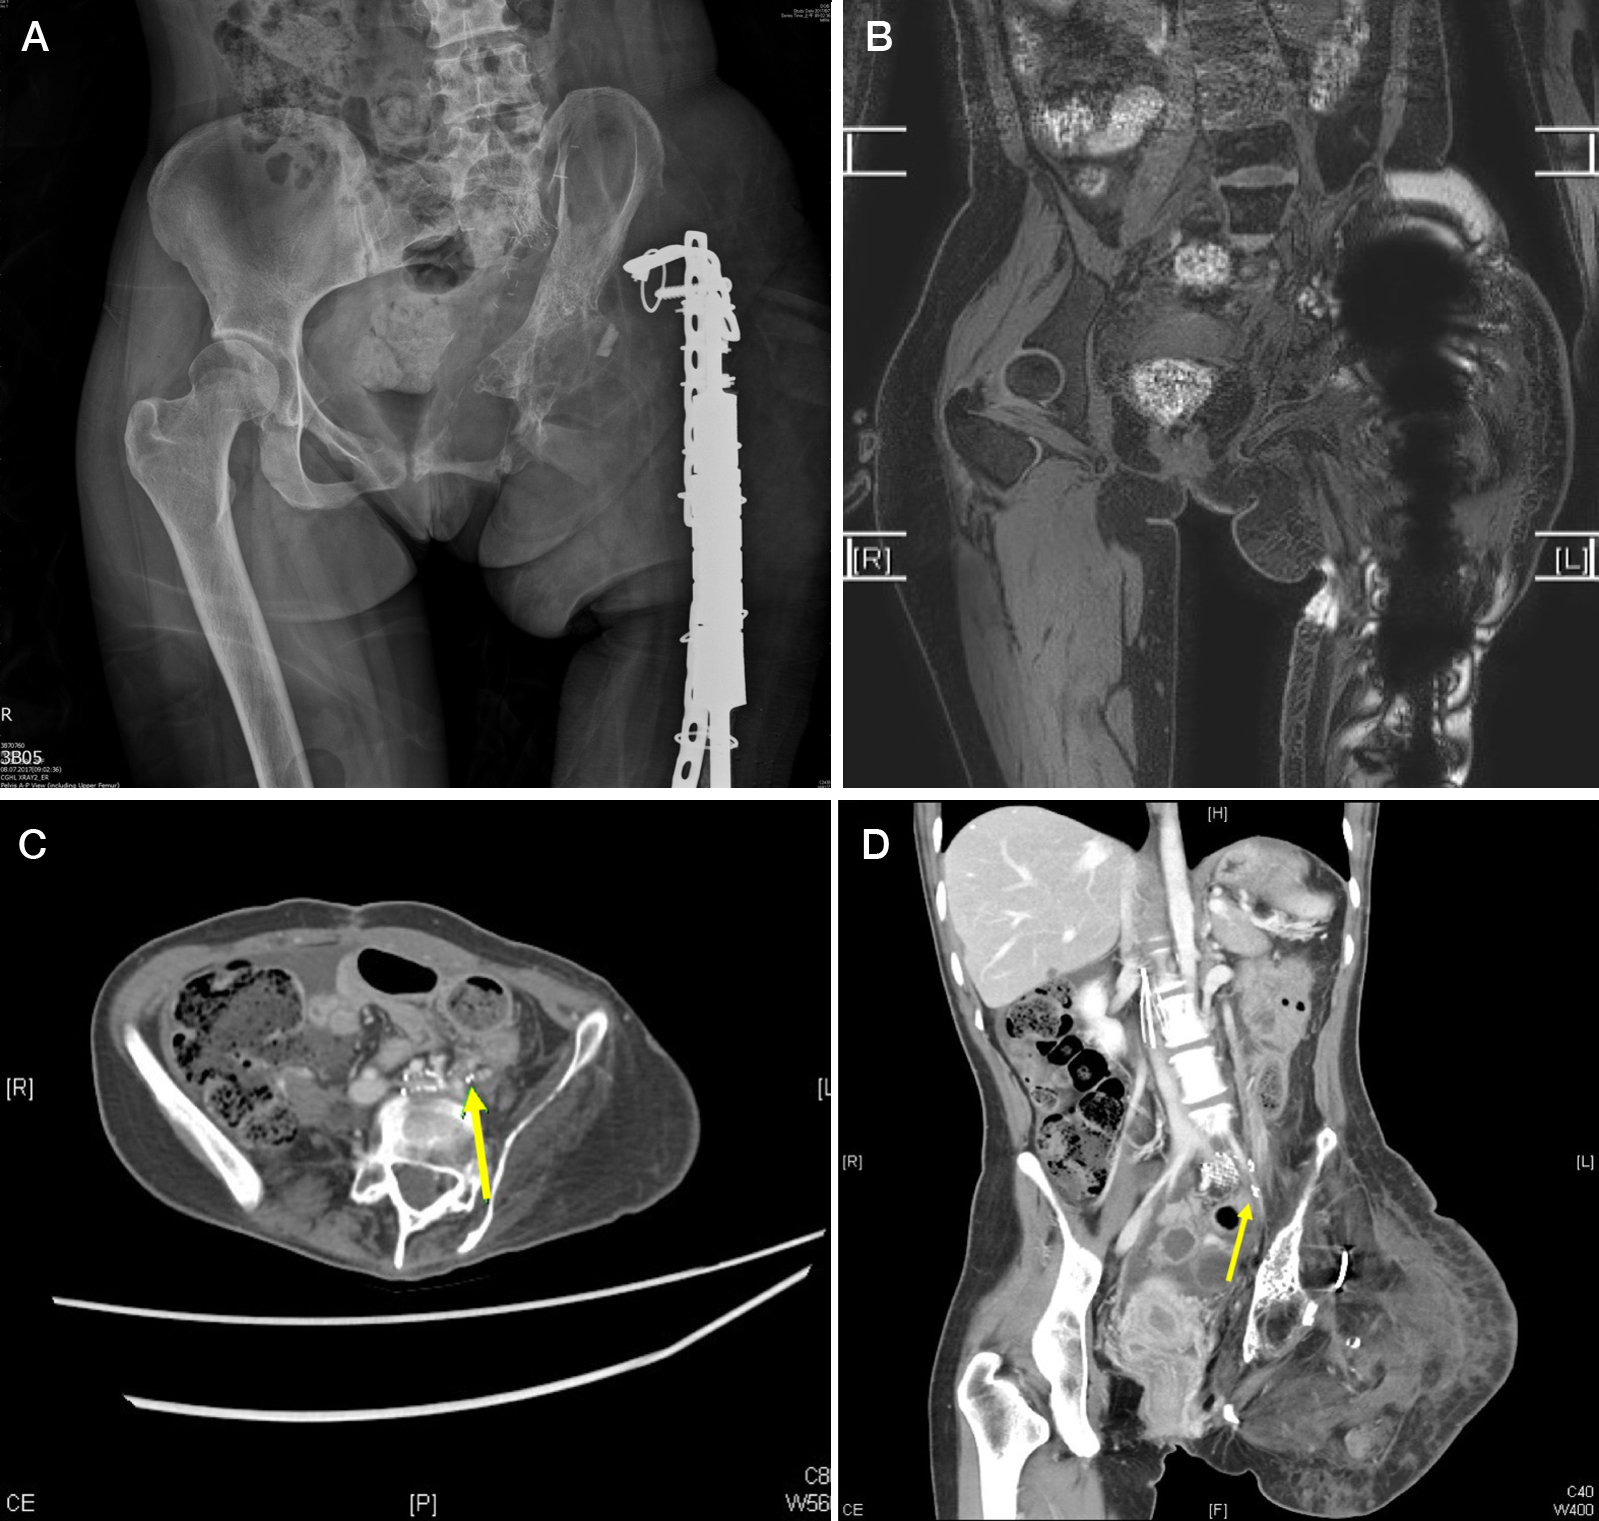

For the diagnosis of retroperitoneal lymphangiomatosis, the methods that are currently being used include direct lymphangiography followed by computed tomography (CT) and magnetic resonance imaging (MRI). Chen et al. performed MRI in patients with primary extremity lymphedema who also presented with abdominal symptoms and/or ascites in order to view extravasation of chyle into the peritoneal cavity. If the examination was positive, a single photon emission CT (SPECT) scan was then performed to visualize the retroperitoneal lymphatic malformation. Seven patients underwent exploratory laparotomy under the suspicion of retroperitoneal lymphangiomatosis, and six were positive, yielding a specificity of 85.7% when both MRI and SPECT were utilized ( Fig. 5.1 ).

For patients whose extremity lymphedema is of Cheng’s Lymphedema Grade II–IV and who present with total obstruction on Tc-99 lymphoscintigraphy or a lack of patent lymphatic ducts on ICG lymphography, VLNT is indicated. For those who have Cheng’s Lymphedema Grade I–II, partial obstruction on Tc-99 lymphoscintigraphy, and patent lymphatic ducts on ICG, LVA is preferred. Cheng et al. found that 84.6% of congenital extremity lymphedema patients required VLNT. Due to the initial severity of primary extremity lymphedema combined with delayed diagnosis and treatment, VLNT may be required in most cases of primary extremity lymphedema ( Fig. 5.2 ).